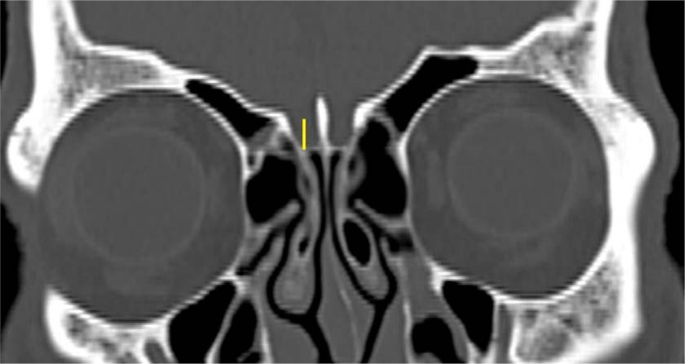

Multiplanar (MPR) CT images were reconstructed to obtain the OF measurement in true horizontal plane in both the coronal and sagittal views. A line drawn along the nasal floor served as the reference point. In the coronal view, the right orbital floor was measured at the point where the right medial wall of the maxillary sinus roof was seen at its maximum height. In the coronal view (Fig. 1), the heights from nasal floor to right ER (labelled A), from nasal floor to right OF (a single view at the maximum height to the right maxillary sinus) (labelled B), and from nasal floor to right CP (labelled C) were measured. Each vertical height was measured 90° perpendicular to the nasal floor. When there was a lower cribriform height at another point anterior to the sphenoid (based on sagittal view), then this was used for the CP height. The measurements were repeated on the left. To assess the risk of skull base injury using the TMS classification, the distances from OF to CP (OF-CP) and from OF to ER (OF-ER) were used. We classified the risk of skull base injury into type 1, type 2 and type 3 (Fig. 2). Type 1 (low risk) is both OF-CP and OF-ER are 10 mm and above, or more than twice the depth of thru-cutting forceps when ESS is considered as safe, type 2 (moderate risk) is when either OF-CP or OF-ER is less than 10 mm, or less than twice of the depth of thru-cutting forceps when ESS should proceed with caution and type 3 (high risk) is both OF-CP and OF-ER are less than 10 mm or less than the depth of thru-cutting forceps when ESS should proceed with extreme caution.

The heights of the ethmoid roof (A), orbital floor (B), and cribriform plate (C) relative to the nasal floor in coronal CT PNS. Each vertical height was measured 90° perpendicular to the nasal floor. To assess the risk of skull base injury using TMS classification, the distances from orbital floor to cribriform plate (OF-CP) and from orbital floor to ethmoid roof (OF-ER) were used. Red asterisk denotes the maximum height of the maxillary sinus which is the level taken as the orbital floor landmark.

The depth of the CP, measured as the vertical height of the olfactory fossa in the coronal plane on each side (Fig. 3), was measured and classified as type 1 (1 to 3 mm depth), type 2 (4 to 7 mm depth) or type 3 (more than 7 mm depth). Asymmetry in the depth (difference of more than 3 mm) between the right and left CPs was also recorded. The measurements were repeated on the left.

Keros classification7 was assessed according to the depth of the cribriform plate, measured as the vertical height of the olfactory fossa in the CT coronal plane and classified as type 1, 2 and 3.